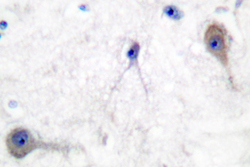

LS-C176173 IHC

Immunohistochemistry